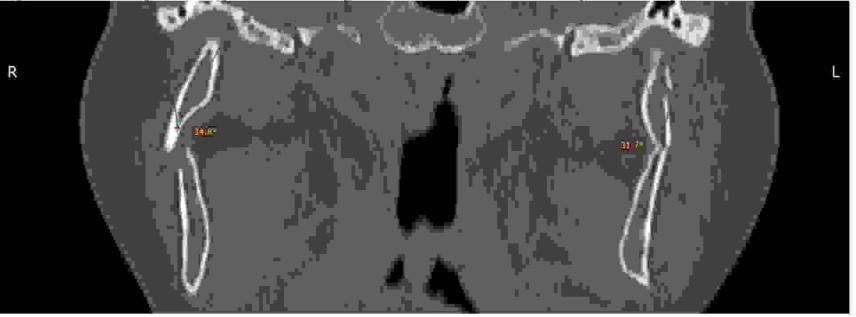

Pacjentka (41 lat) została przywieziona po wypadku komunikacyjnym do SOR. Doznała izolowanego urazu żuchwy. Ma łuki zębowe. Stan ogólny dobry. Na poniższym przekroju wieńcowym otrzymanym ze spiralnej tomografii komputerowej zaznaczone są kąty przemieszczenia w złamaniach podstawy wyrostków kłykciowych żuchwy. Wskaż prawidłową metodę leczenia:

Pytanie 78